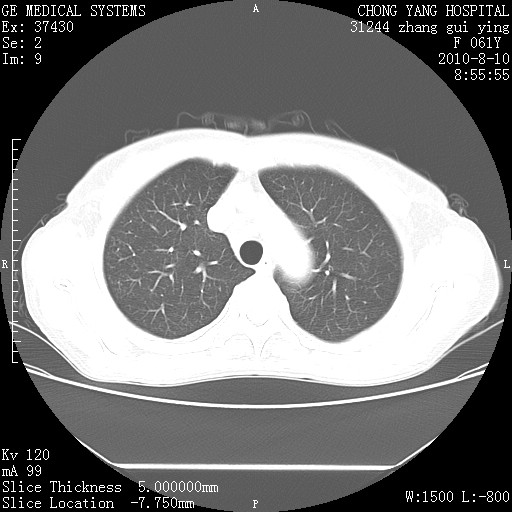

标题: CT28314:F61Y胸部增强,发热咳嗽一周入院,后面的为一周前平

1、支持考虑右侧中央型肺癌伴右肺中叶节段性不张及下叶支气管黏液痰栓    2、左肺上叶舌段感染。

支持右下肺中央型肺癌并左上肺感染.

我也觉得右肺中叶支气管受累

确切的说:1:右肺下叶中心型肺癌侵及中叶支气管并中叶不张,纵膈淋巴结转移。2:左肺舌叶炎症。3:右侧胸腔少量积液

1:右肺下叶中心型肺癌侵及中叶支气管并中叶不张,纵膈淋巴结转移。2:左肺舌叶炎症。3:右侧胸腔少量积液。支持!